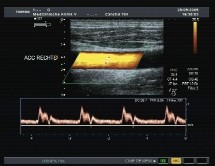

Sonographie:

• Systolische Dopplerdruckmessung

• cw-Dopplersonographie

• B-Bild-Sonographie

• (Farb-) Duplexsonographie

• Kontrastmittel-verstärkte Sonographie

Ultraschalldiagnostik

Im hochauflösenden Schwarz-Weiss-Bild (B-Bild) können die Arterien und Venen in ihren beschallbaren Verlaufsabschnitten direkt dargestellt und möglichst langstreckig verfolgt werden. Krankhafte Veränderungen der Gefäßwand, speziell atherosklerotische Wandverdickungen, Auflagerungen und Gerinnselbildungen (Thromben) können auf diese Weise erfaßt werden. Mittels Plaque- und Stenosemessungen kann der Schweregrad bestehender Gefäßverengungen ermittelt werden.

Im Farbduplex-Verfahren werdendie Blutflüsse in den Arterien und Venen jeweils farbig dargestellt und mittels Strömungskurven (pw- und cw-Doppler) vermessen werden. Mit modernen Ultraschallgeräten ist es möglich, selbst langsamste Strömungen mit speziellen Verfahren (Digital-Power-Imaging, Power-Mode, Angio-Mode) farbig darzustellen und zu beurteilen.

Zusätzlich können zur verbesserten Kontrastdarstellung bei Erfordernis Signalverstärker (Ultraschallkontrastmittel) eingesetzt werden. Im Unterschied zu Röntgenkontrastmitteln sind diese Ultraschallkontrastmittel völlig gefahrlos und frei von Nebenwirkungen (keine Jodüberladung, keine Allergien, keine Schockgefahr, keine Strahlenbelastung).

Ein Gefäß-Check mit Ultraschall ermöglicht im einzelnen die Beurteilung der folgenden Gefäße: Sämtliche beschallbaren hirnversorgenden Blutgefäße des Halses und des Schädelinneren, sämtliche beschallbaren Blutgefäße der Arme und Beine bis zu den Fingern und Zehen, sämtliche beschallbaren Blutgefäße des Bauchraumes einschließlich Bauchaorta, Becken-, Nieren- und Genitalgefäßen.